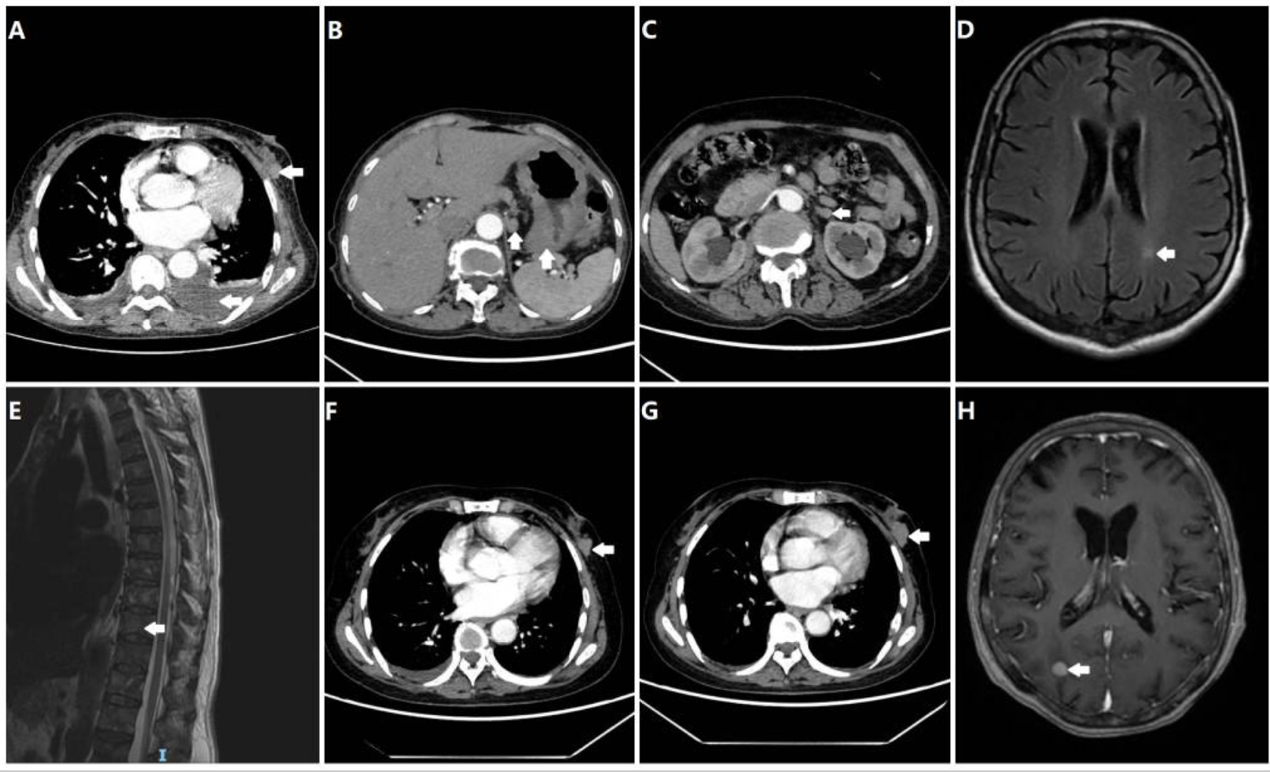

患者为一名68岁绝经后女性,因“胸闷一周”于2024年2月就诊于南京市高淳人民医院。入院初步CT检查提示:左乳可见一大小约4.0厘米的不规则肿块,符合乳腺影像报告和数据系统(BI-RADS)5级标准(9),伴有同侧腋窝淋巴结肿大、双侧胸腔积液及心包积液(图1A)。为明确分期,后续进行了系统性影像学评估,结果显示存在广泛转移,包括胃壁弥漫性增厚(图1B)、左侧肾上腺结节(图1C)、脑内强化灶(图1D)以及溶骨性骨破坏(图1E)。

A) 胸部CT显示左侧乳房肿块(箭头所示),伴有局部皮肤增厚和左侧胸腔积液。(B) 胃壁增厚,伴胃周淋巴结肿大。(C) 肾上腺转移性结节。(D) 左侧枕叶脑转移灶。(E) 脊柱和椎体附件多发性转移灶。(F) 经过两个周期的一线化疗后,乳腺癌病情稳定。(G) 乳腺癌疾病进展。(H) 右侧大脑出现新发颅内转移灶。所有图像中的白色箭头均指示肿瘤位置。

确诊后,患者于2024年2月开始接受一线化疗,方案为“紫杉醇(175 mg/m²,第1天)联合卡培他滨(1000 mg/m²,每日两次,第1-14天),每21天一周期”(TX方案)。治疗2周期后复查,疗效评价为疾病稳定(SD)(图1F)。完成6周期化疗后,患者进入卡培他滨单药(剂量同前)维持治疗阶段,并定期进行影像学监测。

2025年2月,复查提示疾病进展(PD)(图1G),遂更换为二线优替德隆单药(30 mg/m²,第1-5天,每21天一周期)治疗。然而,2025年5月再次复查发现,患者出现新的颅内转移灶(图1H),并伴有头晕症状,临床判断为再次进展。